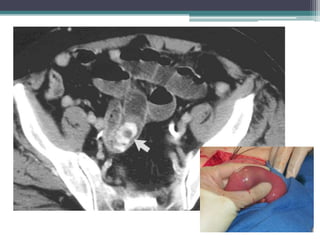

Tài liệu bàn về tắc ruột, bao gồm định nghĩa, phân loại và nguyên nhân của tình trạng này, với sự phân biệt giữa tắc cơ học và cơ năng. Các triệu chứng và chẩn đoán lâm sàng được trình bày, kèm theo phương pháp chẩn đoán cận lâm sàng như x-quang và siêu âm. Ngoài ra, tài liệu cũng đề cập đến các biến chứng và hậu quả của tắc ruột.